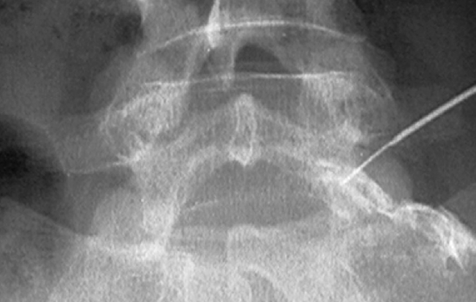

경막외 신경성형술

감압신경 성형술이라고도 불리는 치료법으로 지름이 1mm 정도의 아주 작은 카테터관을 신경과 디스크 사이로 정확하게 삽입해 통증의 원인인 염증을 제거하고 유착을 박리해 통증을 없애는 치료입니다. 짧은 시술시간과 시술에 따른 부작용이나 합병증이 거의 없으며 바로 일상생활 복귀가 가능해 디스크의 대표적인 비수술적 치료방법으로 여겨지고 있어요.